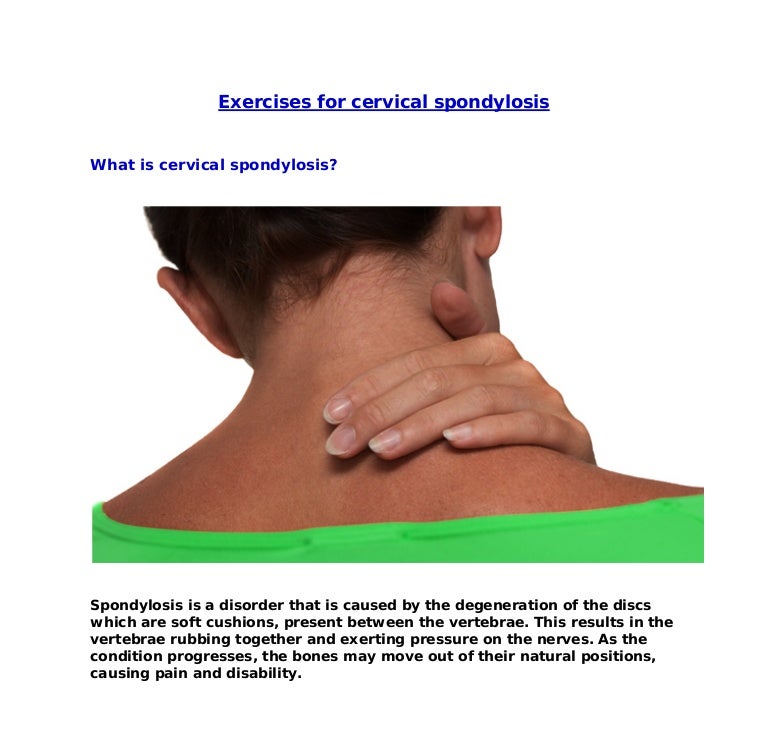

Exercises For Cervical Spondylosis